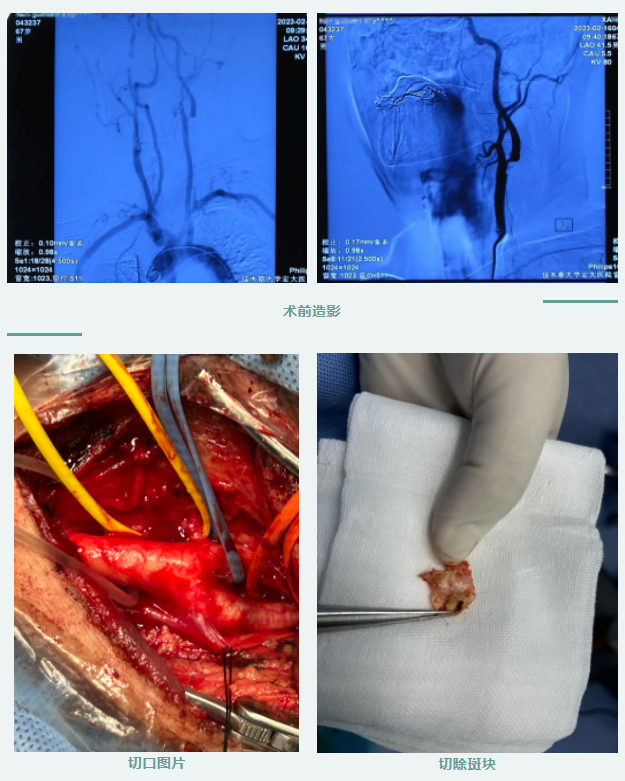

近七旬的患者劉先生,因“頭暈乏力、上肢無知覺”來到我院就診,經(jīng)雙側(cè)頸動(dòng)脈超聲檢查提示:雙側(cè)頸部動(dòng)脈粥樣硬化性斑塊形成伴局部管腔狹窄,為進(jìn)一步明確診斷,在神經(jīng)介入內(nèi)二科艾長(zhǎng)思主任的帶領(lǐng)下,又為劉先生進(jìn)行了腦血管造影檢查,最終確診為“重度左側(cè)頸內(nèi)動(dòng)脈狹窄”。陳虹院長(zhǎng)帶領(lǐng)神經(jīng)內(nèi)科介入治療團(tuán)隊(duì)對(duì)該患者進(jìn)行了會(huì)診,經(jīng)全面評(píng)估,決定為其實(shí)施“頸動(dòng)脈內(nèi)膜剝脫術(shù)”,并為患者制定了縝密的手術(shù)方案。繼而,再一次開展了團(tuán)隊(duì)醫(yī)護(hù)人員專項(xiàng)救治培訓(xùn),經(jīng)過與患者及家屬有效溝通,確定了治療方案。

術(shù)前,醫(yī)護(hù)人員對(duì)患者進(jìn)行詳細(xì)檢查,結(jié)合患者斑塊形狀以及周圍組織關(guān)系等,積極做好各項(xiàng)準(zhǔn)備工作;術(shù)中,艾長(zhǎng)思主任團(tuán)隊(duì)在麻醉科和手術(shù)室的密切配合下,為患者進(jìn)行頸動(dòng)脈內(nèi)膜剝脫手術(shù),取左側(cè)胸鎖乳突肌前緣斜切口,長(zhǎng)約7cm,上段至下頜角水平上方2cm,打開頸動(dòng)脈鞘,顯露頸總動(dòng)脈分叉部及頸內(nèi)、頸外動(dòng)脈分支,可見頸內(nèi)動(dòng)脈起始部斑塊。鈍性分離切除頸總遠(yuǎn)端及頸內(nèi)、頸外動(dòng)脈近端內(nèi)膜斑塊,肝素鹽水沖洗,縫合動(dòng)脈切口,依次開放頸外、頸總及頸內(nèi)動(dòng)脈血流。此次手術(shù)歷時(shí)1小時(shí),成功剝脫了患者頸動(dòng)脈斑塊,使病變的頸動(dòng)脈重新恢復(fù)暢通與活力。